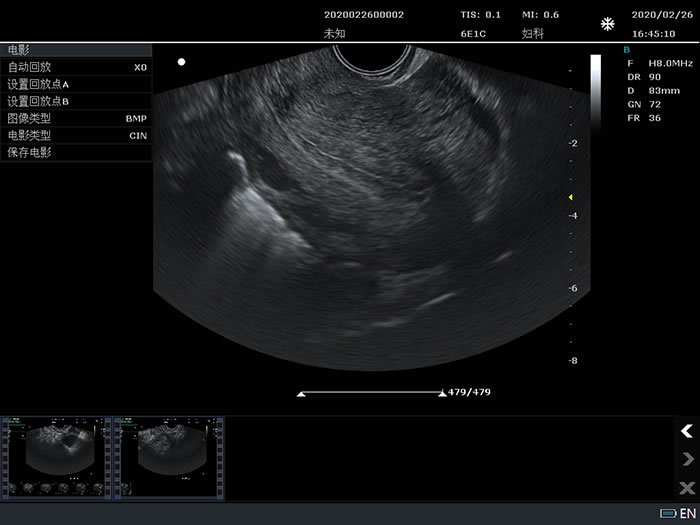

妇科B模式应用测量

6E1C: 6.5MHz/R10/128阵元腔内探头;